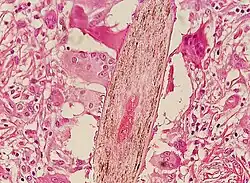

Chronic folliculitis surrounding central sebaceous hyperplasia, right mid-chest